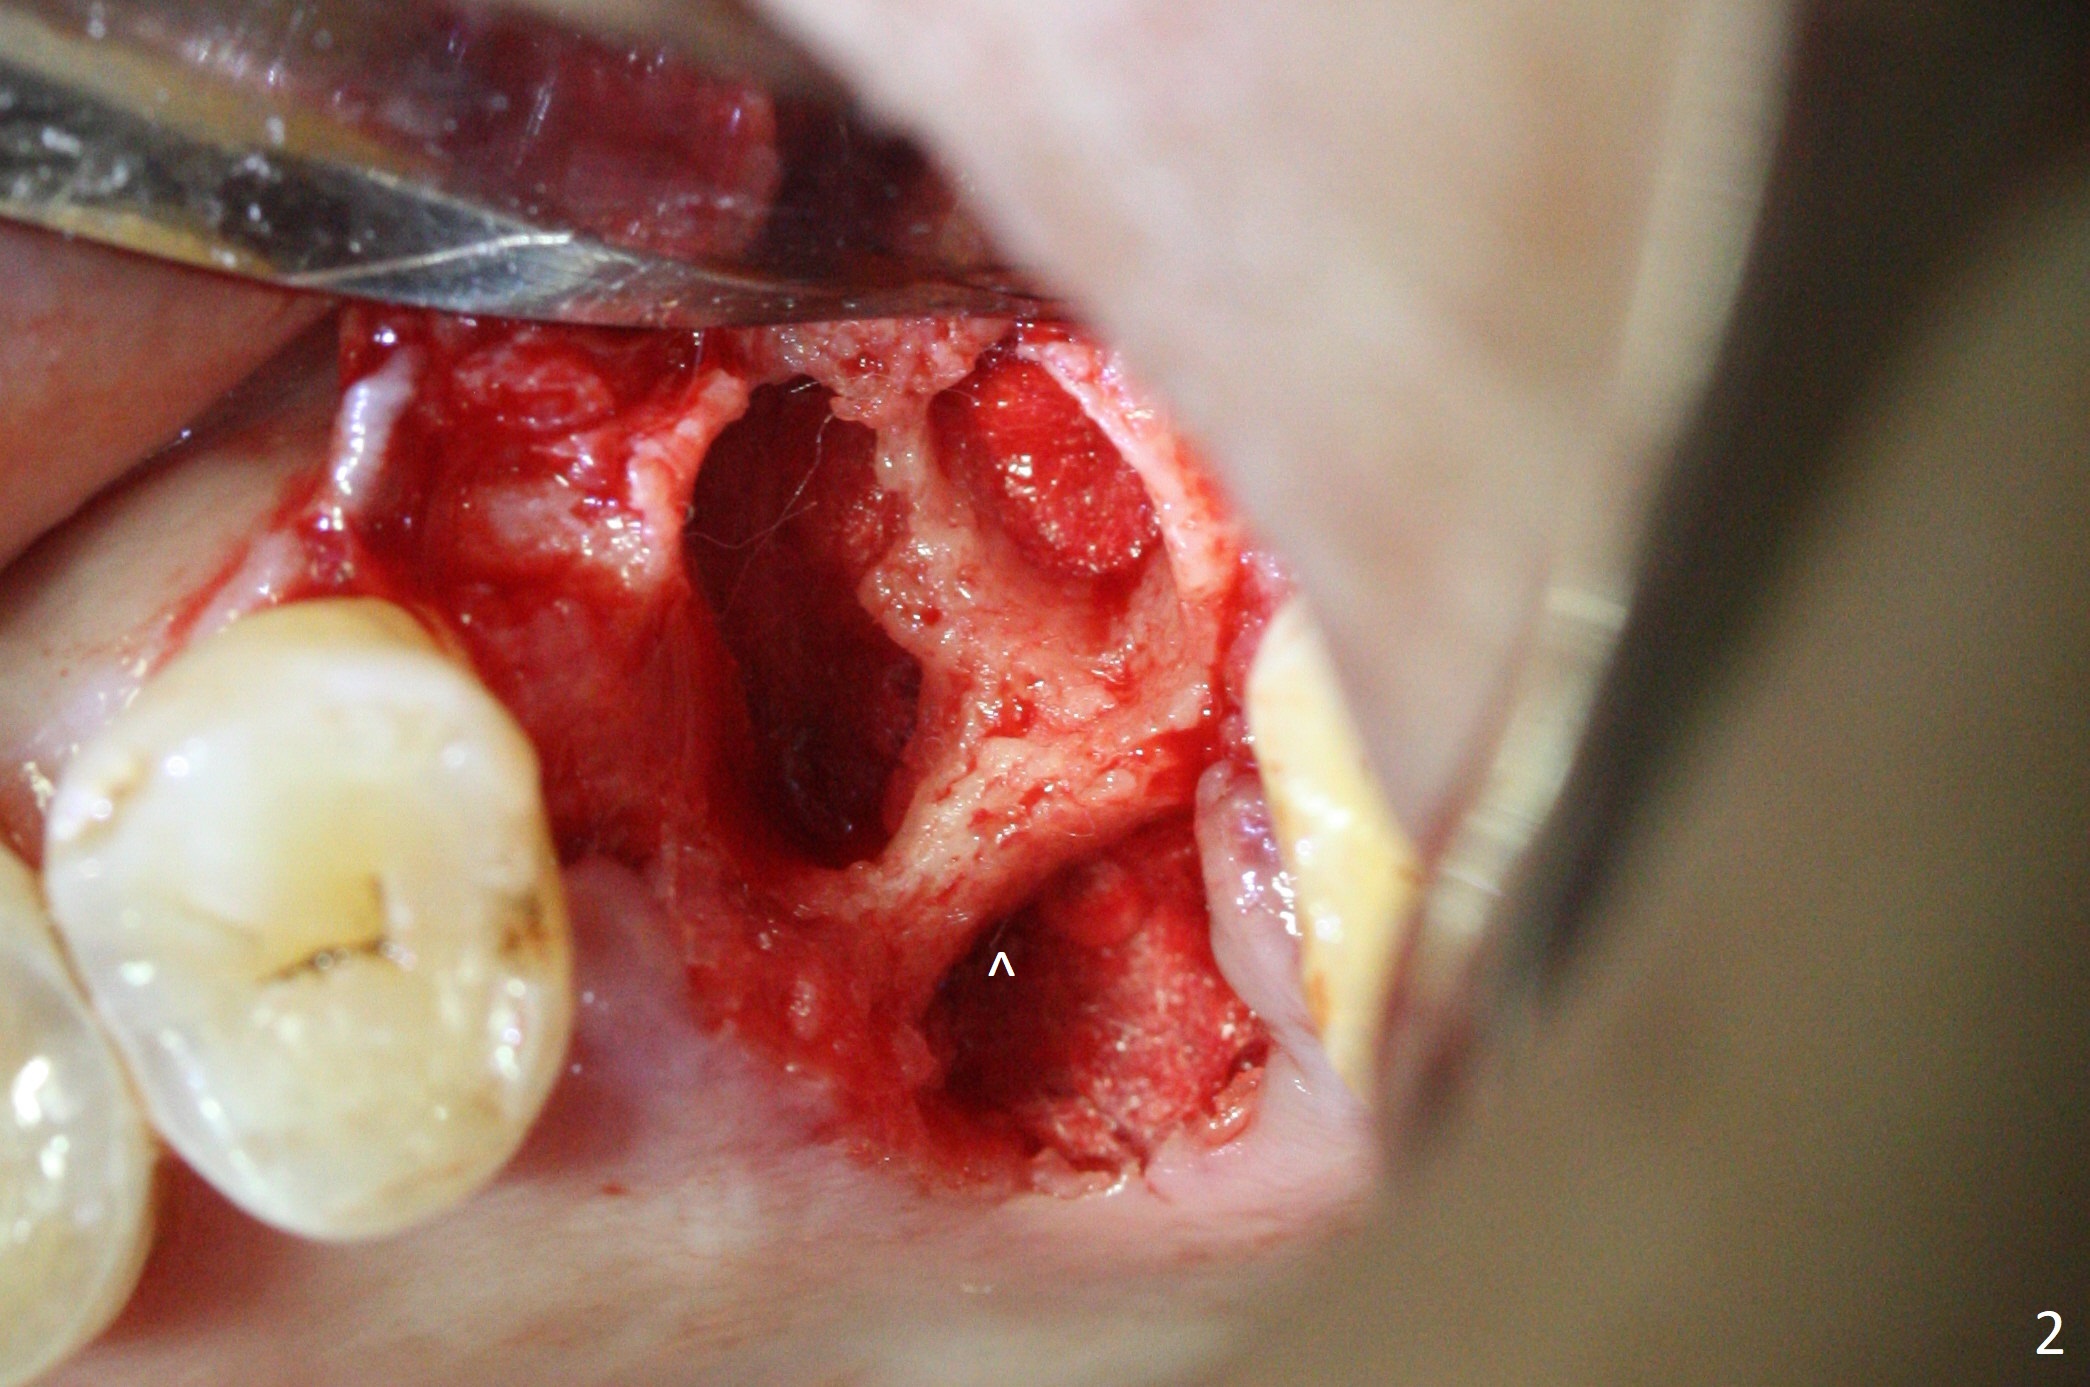

After extraction of the tooth #14 with palatal root fracture (Fig.1 <), sinus membrane perforation is found in the buccal wall of the palatal socket (Fig.2 ^). Osteotomy is initiated in the buccal strut of the septum (Fig.3 *). As the osteotomy increases in diameter, it slides into the mesiobuccal socket (Fig.4). A 5x9 mm implant is placed slightly mesial; after placement of a 6.5x4(2) mm abutment and insertion of collagen plug in the palatal socket, Vera graft is placed in the remaining socket space (Fig.5 *). Nasal hemorrhage persists 1.5 months postop (Fig.6). The distal gingiva is slightly tender and erythematous; a 6x4 mm healing abutment is placed 2.5 months postop (Fig.7,8). Impression is taken after laser gingivectomy 3.5 months postop. The patient feels discomfort at the site 7 days post impression, although the gingiva heals after laser treatment. Two weeks after cementation, the mesial gingiva is mildly tender and the abutment screw is loose. A 6x3 mm healing abutment is placed. The abutment/crown is reseated 10 months postop (Fig.9).